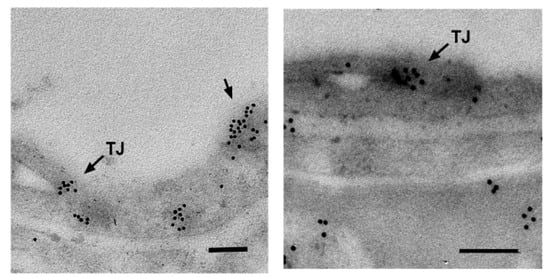

- Jurkiewicz, D.; Michalec, K.; Skowronek, K.; Nałęcz, K.A. Tight junction protein ZO-1 controls organic cation/carnitine transporter OCTN2 (SLC22A5) in a protein kinase C-dependent way. Biochim. Biophys. Acta 2017, 1864, 797–805. [Google Scholar] [CrossRef] [PubMed]